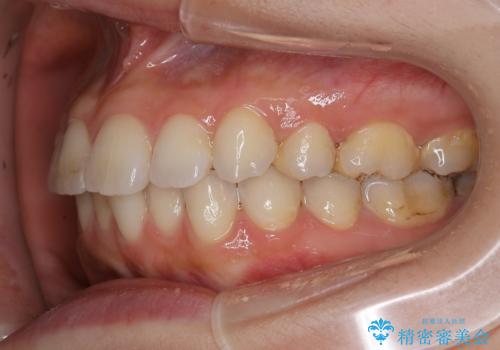

前歯のガタつきを改善 抜歯矯正後の後戻り

- 抜歯矯正後の後戻りで前歯ガタつきが主訴で来院された患者様です。

後戻りの程度としては軽度なので、治療期間としては短く終えることが出来ました。

前歯の正中線も改善され大変満足して頂きました。